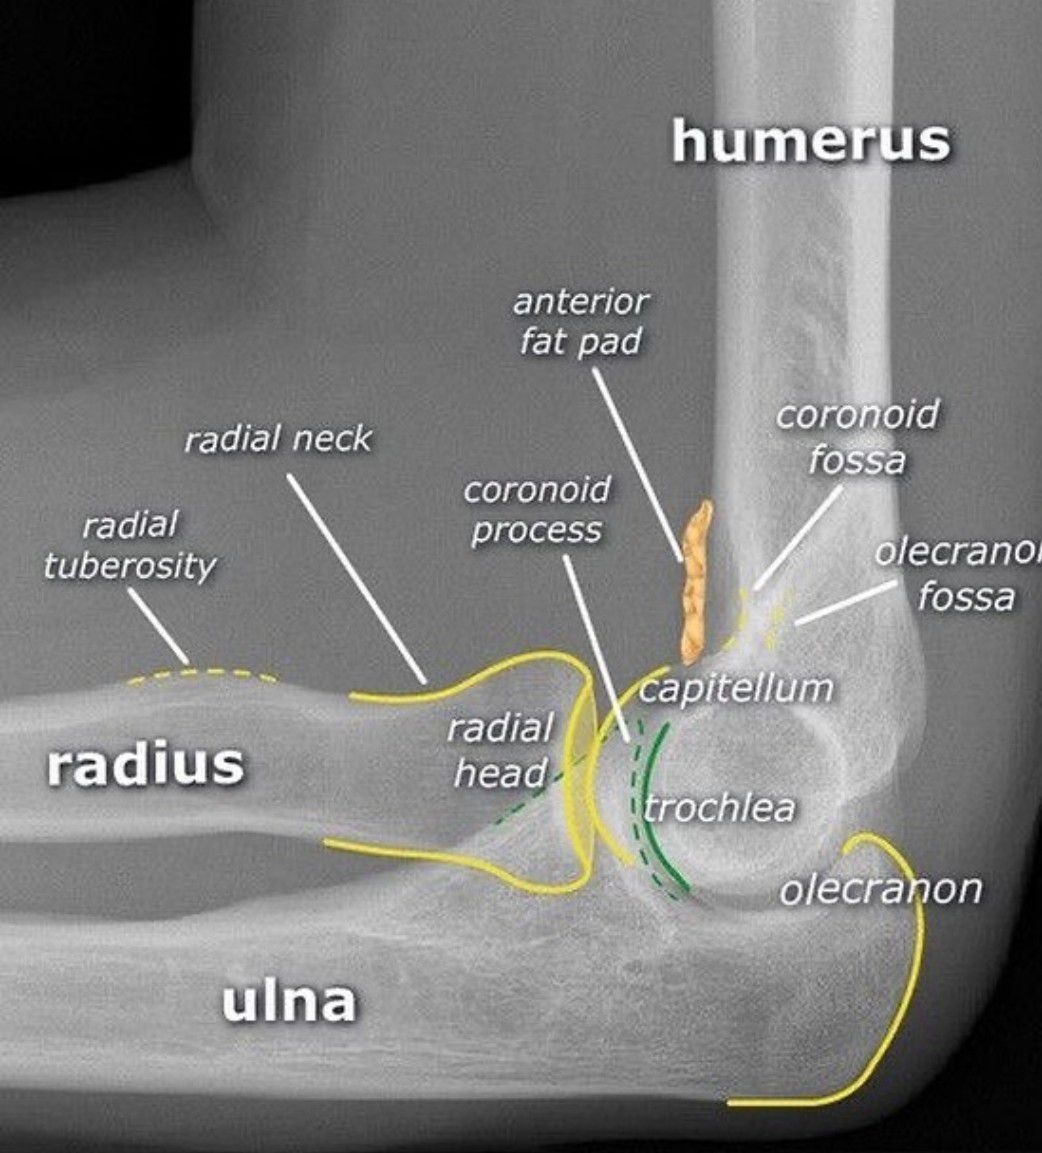

Elbow Joint Radiology

Elbow joint radiology is shown here